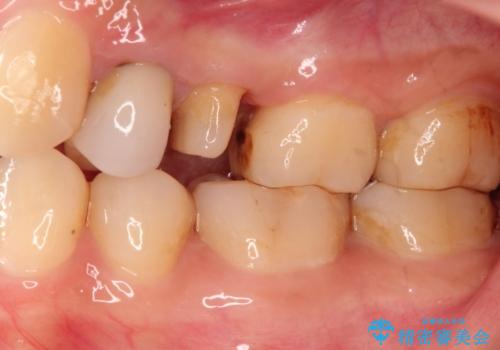

- 歯が欠けたとのことで来院されました。

過去に治療してあった左上の歯が一部欠けていました。

かぶせ物と詰めてある修復物を除去すると歯肉の中まで虫歯になっていました。

歯を部分矯正で引き上げて、虫歯を徹底的に取り除き、適合の良いかぶせ物を装着する計画としました。